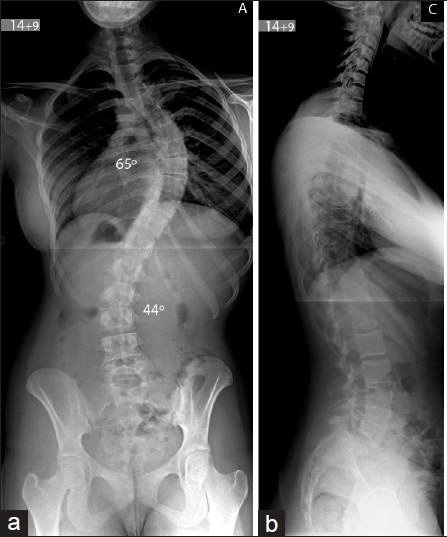

Откуда берётся сколиоз?

Привет, дорогие читатели! В последнее время ко мне приходит всё больше запросов на коррекцию сколиоза. При этом в большинстве случаев данный диагноз обоснован только беглым взглядом врача на медосмотре и фразой: "О, да у вас сколиоз!" В наше время, когда мы проводим огромное количество часов за компьютерами и мобильными устройствами, искривление позвоночника стало настоящим бедствием. Однако, не каждый перекос плеч и сутулость являются сколиозом. Давайте разбираться. Сколиоз — это искривление позвоночника в трёх плоскостях с обязательной ротацией позвонков (если ротации нет, то это уже не сколиоз). Важно понимать, что это деформация костных структур, а не просто следствие разного тонуса мышц, как вы могли слышать. При этом наиболее распространённый диагноз — "идиопатический сколиоз" — ставится в 70% случаев, и его происхождение до сих пор остаётся загадкой. Известно, что сколиоз может передаваться по наследству, ему больше подвержены девочки, а из-за быстрого роста прогрессия чаще в